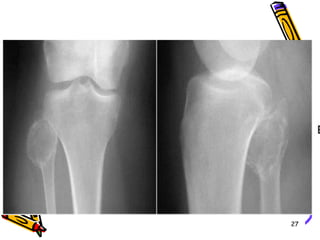

51 year old lady  c/o knee pain88

T1 weighted MRI revealed lesion within fibula and no breaching of cortex89

Primary resection was done without biopsy 90

This treatment strategy allowed for wide marginal excision without contamination of common peroneal nerve Lesion proved to be low grade  chondro sarcoma 91

92